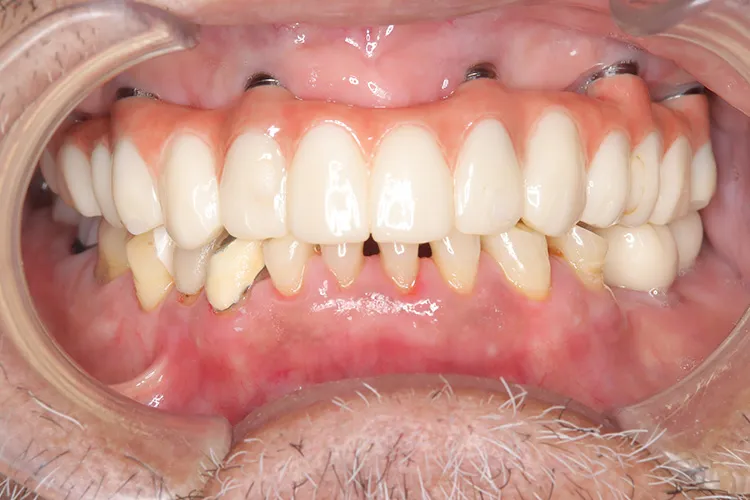

歯ぎしり・食いしばりが強い方の治療ケースです。全体的に歯が擦り減り正面から見て下の歯が見えないほど噛み合わせの高さが失われており、顎関節にも症状がでていました。ヒビが入って保存不可の歯を抜歯しインプラントを計5本埋入し、前歯・臼歯にインプラント土台のブリッジを入れることで噛み合わせの高さを回復しました。古い金属の被せ物もジルコニアでやりかえました。噛み合わせの高さが改善したことで顎関節症状もなくなり快適に過ごされています。歯ぎしりがある方は、夜間のナイトガード装着が必要になります。